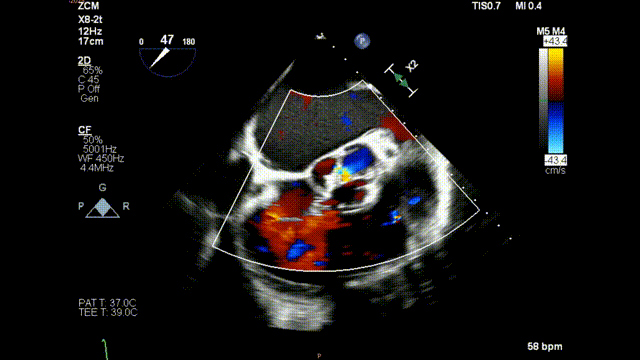

术前食道超声示:

术前食道超声-短轴color

术前食道超声-长轴color

术前食道超声-短轴 color

术前食道超声-长轴 color